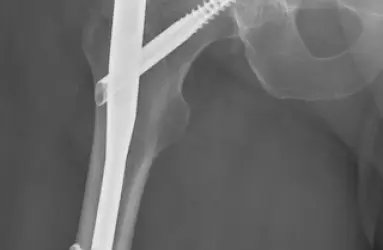

- Total Eklem Protezi (Kalça, diz, diğer)